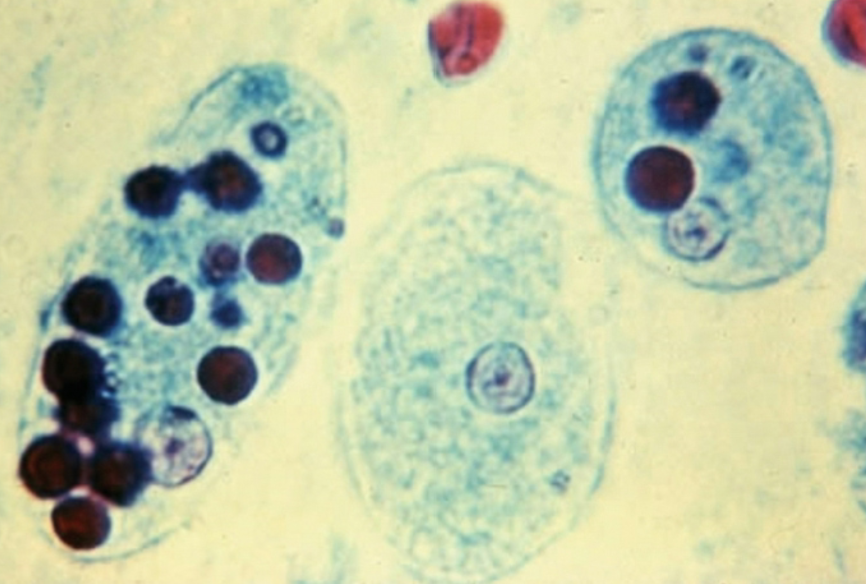

Toxoplasma gondii Oocysts

Toxoplasma gondii Tachyzoites

Sacrocystis Sporocysts

Sacrocystis